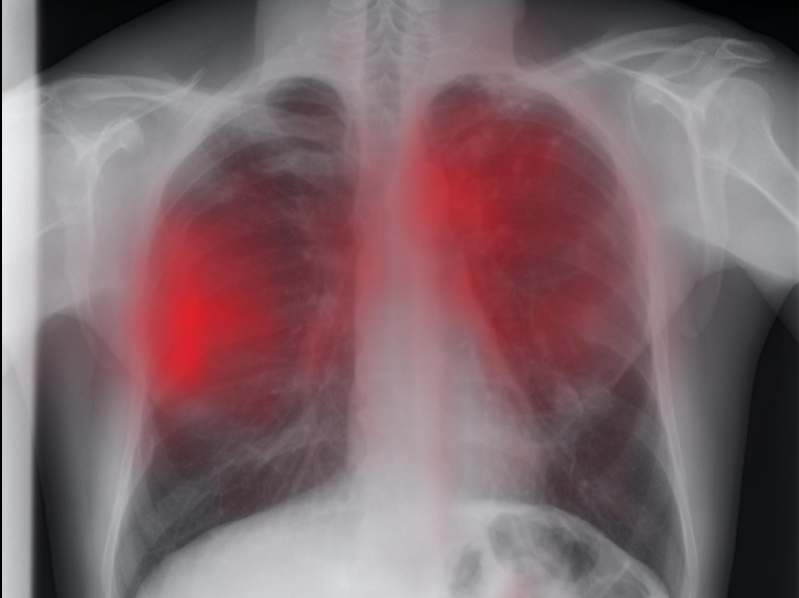

Numărul cazurile de tuberculoză din județul Iași a crescut ca urmare a relaxării măsurilor luate în starea de urgență generată de pandemia Covid și instalarea stării de alertă. Numai într-o singură zi la Iași au fost înregistrate 10 cazuri de tuberculoză.

”Accesul pacienților a fost dificil în contextul pandemiei și numărul lor a fost foarte mic. Până la data de 16 martie înregistrasem 130 de cazuri de tuberculoză. De la data de 16 martie și până astăzi am înregistrat 74 de cazuri. Dar numărul foarte mare a apărut după data de 1 iunie, când lumea s-a relaxat, să spunem, a devenit mai încrezătoare că poate să circule pe străzi și că se poate adresa unităților sanitare. În consecință, s-a prezentat la dispensarele TBC sau la alte unități medicale și de acolo s-a ajuns la noi. Noi am depistat acest număr de 74 de cazuri de tuberculoză, jumătate dintre ele sunt cavitare și mai bine de jumătate sunt înalt contagioase. Astfel, 38 din 74 sunt molipsitoare înalt și 31 din 74 sunt cu caverne, deci forme foarte grave de tuberculoză care pun în pericol destul de mare comunitățile în care trăiesc și familiile lor, în primul rând. Pun în pericol locurile de muncă unde se duc, iar cheltuiala cu spitalizarea, tratamentul și vindecarea acestor cazuri va fi mai mare pentru că ei vor avea nevoie de un tratament puțin mai lung decât cel standard. (…) Numai ieri am avut zece cazuri înregistrate. Este foarte mult”, a declarat în exclusivitate pentru Sănătatea Press Group, dr. Sorete Arbore Adriana, coordonatorul județean din cadrul Programului Național TB.

”În fiecare județ sunt dispensare TBC, în orașele mari există aceste unități. Radiografia este în regim gratuit, nu contează dacă ești asigurat sau nu. Dacă ești simptomatic respirator te poți adresa pentru investigații de bază, examenul bacteriologic al sputei și radiografie. Nu trebuie așteptat să treacă aceste simptome pentru că te pui în pericol pe tine și îi pui în pericol și pe ceilalți”, a mai adăugat dr. Sorete Arbore pentru Sănătatea Press Group.